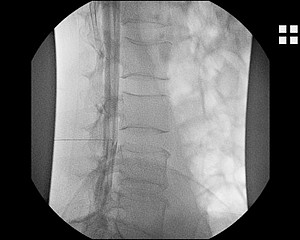

Nach Hautdesinfektion am Rücken wird mit einer Nadel der Nervenwasserraum der Lendenwirbelsäule punktiert und in diesen ein Kontrastmittel injiziert.

Da das Kontrastmittel sich im gesamten Nervenwasserraum verteilt, können sowohl die Hals-, die Brust- und die Lendenwirbelsäule anschließend untersucht werden.